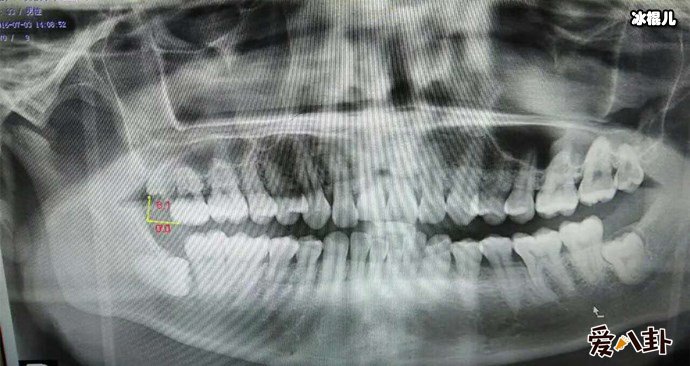

X光下的智齿

说到智齿也就是人们说的智慧齿,智齿实际上是口腔中的第三大臼齿(一般人都有第一和第二大臼齿),因为张智齿的年龄大都是在刚成年的时候,有了智慧所以俗称智慧齿,一般来说有四只智慧齿分别形成始于上下颚骨中,智齿跟其他牙齿一样,但是智齿很不一样的是智齿是最后长出的臼齿,一般智慧齿成形成于9岁而齿冠则于大约14岁形成,并在青春期末长出于口腔中。

不少人都被智齿折磨的痛不欲生,所以么长智齿疼又应该怎么办呢,有这么一个小窍门,如果疼的时候可以含点冰块缓解疼痛,或者用冰块在脸部外敷,一般平时在饮食上要注意,吃的太辛辣就会加重疼痛感,而且每天都要注意清洗口腔,避免口腔滋生细菌,导致长智齿的部位发生感染,一般来说长智齿了就应该马上去医院处理拔掉它,不然智齿压迫了神经,不处理就会遭受长期的疼痛折磨还有进一步加重